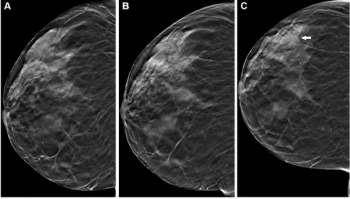

In a large retrospective study involving over 523,000 digital breast tomosynthesis (DBT) exams and over one million digital mammography (DM) exams, researchers found that DBT was associated with significantly lower recall rates but showed no advantage over DM in the diagnosis of interval or advanced breast cancer.